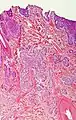

Nodular basal-cell carcinoma

.jpg.webp)

Nodular basal-cell carcinoma (also known as "classic basal-cell carcinoma") accounts for between 50% and 80% of all BCC.[2] It most commonly occurs on the sun-exposed areas of the head and neck.[2] Histopathology shows aggregates of basaloid cells with well-defined borders, showing a peripheral palisading of cells and one or more typical clefts.[17] Such clefts are caused by shrinkage of mucin during tissue fixation and staining.[18] Central necrosis with eosinophilic, granular features may be also present, as well as mucin. The heavy aggregates of mucin determine a cystic structure. Calcification may be also present, especially in long-standing lesions.[17] Mitotic activity is usually not so evident, but a high mitotic rate may be present in more aggressive lesions.[17] Adenoidal BCC can be classified as a variant of NBCC, characterized by basaloid cells with a reticulated configuration extending into the dermis.[17]

Cleft.